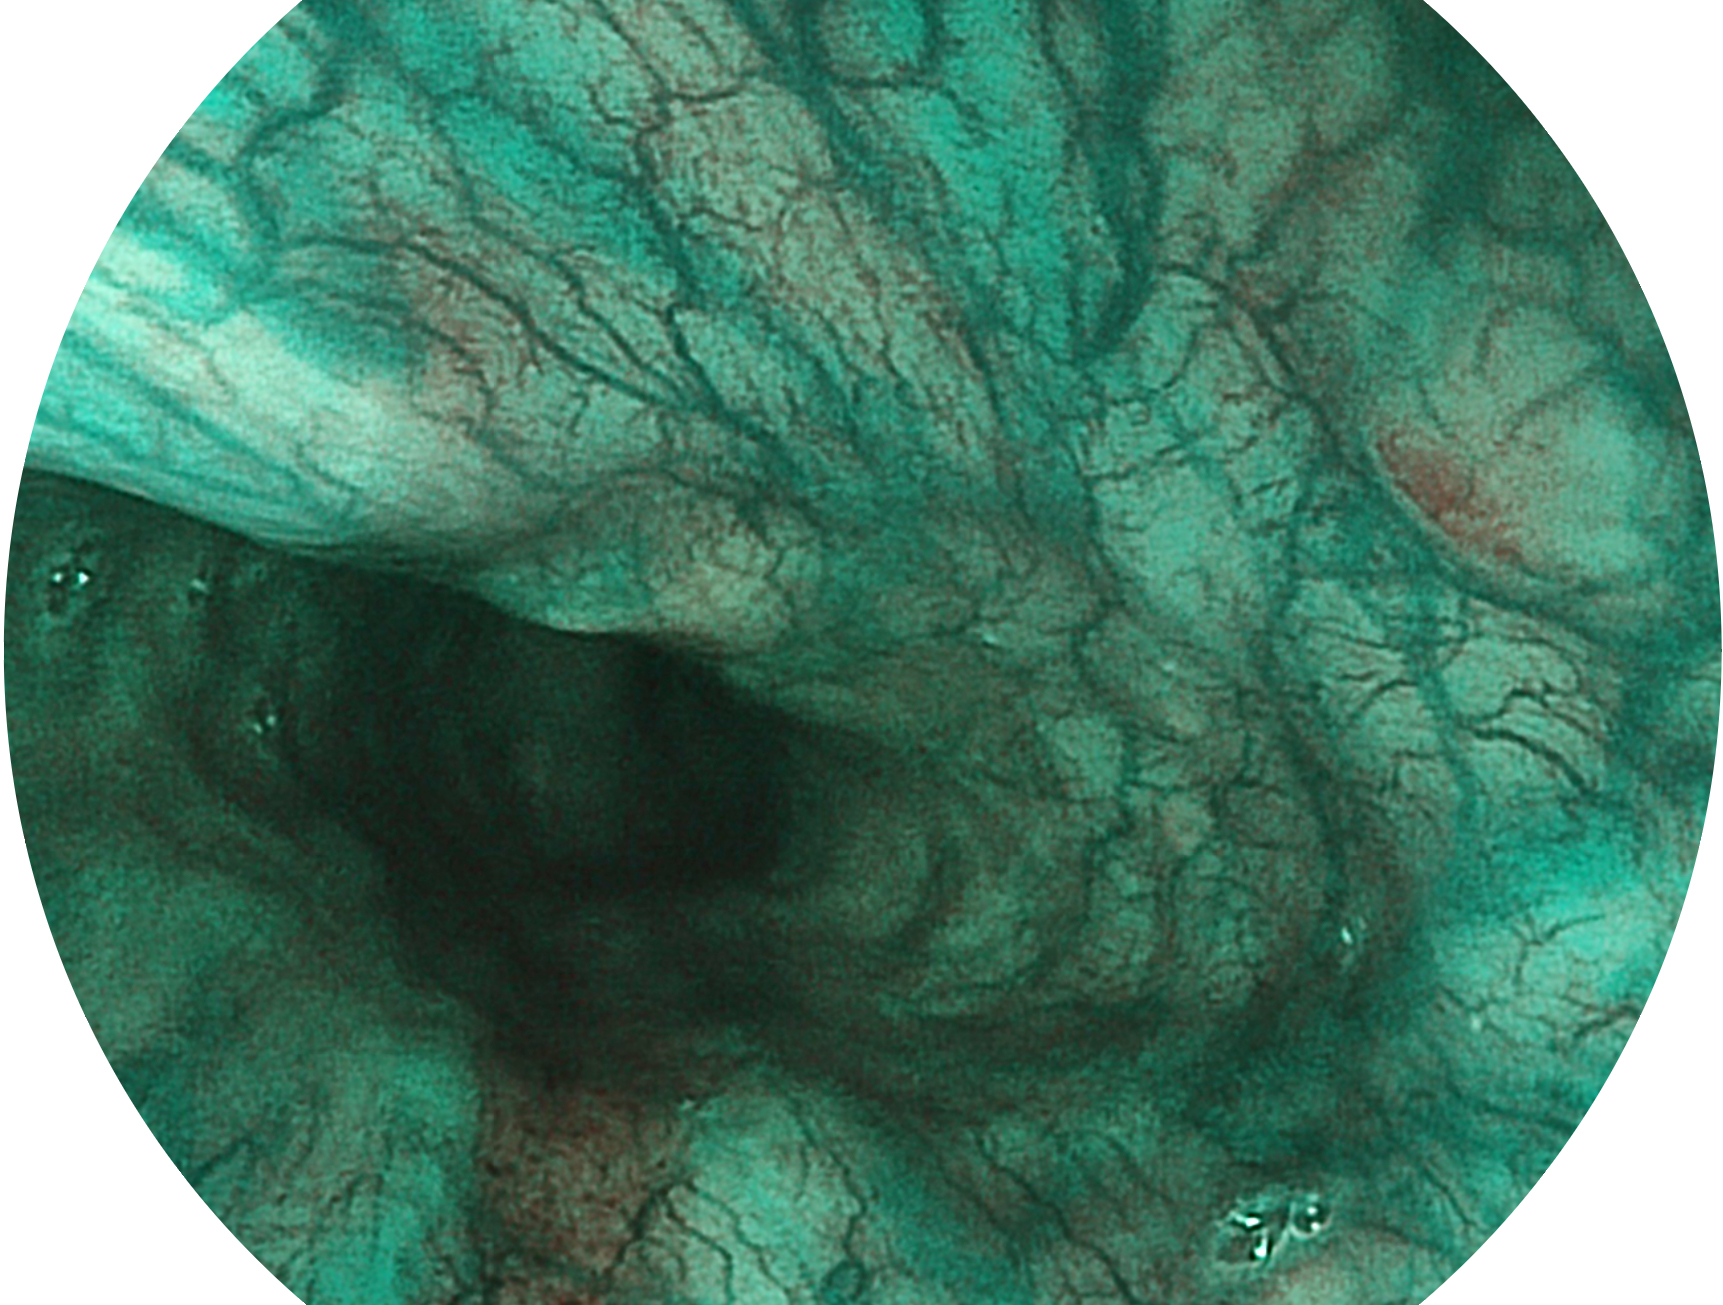

• 白光图像 VIST图像